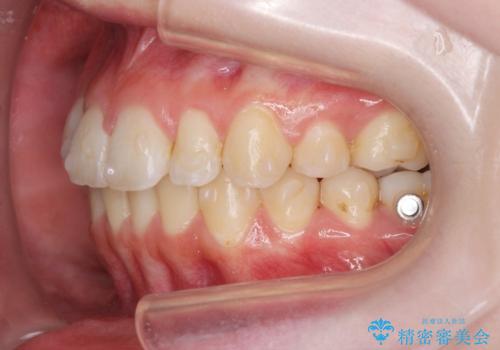

- 前歯の角度 奥歯の噛み合わせの改善をするために、矯正治療を希望され来院されました。

右側奥歯は上顎が相対的に前方に位置し(上顎前突)、そのため前歯の角度も突き出たようになり出っ歯のように見える状態でした。

マイクロインプラントを用いて、上顎奥歯を後方に移動させることで噛み合わせ・前歯の角度を改善していきます。